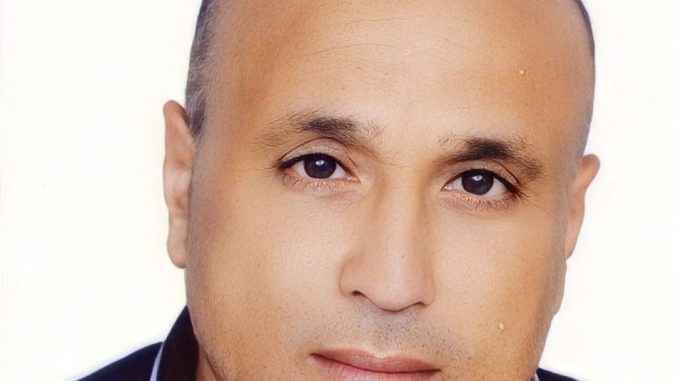

أكد خالد فتحي، الأستاذ بكلية الطب بجامعة محمد الخامس بالرباط والباحث في القضايا الصحية، أن المملكة تسير بخطى ثابتة نحو إنجاح حملة التلقيح الوطنية ضد كوفيد-19.

وبخصوص توسيع حملة التلقيح لتشمل المرضعات والحوامل ابتداء من الشهر الرابع، أفاد الأستاذ فتحي، في تصريح لإذاعة الأخبار المغربية، بأن هذا القرار جاء بعد تأكد اللجنة العلمية من أن اللقاح المضاد لكوفيد-19 فعال وآمن بالنسبة لهاتين الفئتين، وأنه لا يشكل أي خطر على المرأة الحامل أو جنينها.

ودعا الخبير جميع النساء الحوامل للإسراع بتلقي اللقاح من أجل حماية أنفسهن وجنينهن، لاسيما خلال فصل حملهن الأخير، إذ أن الإصابة بكوفيد-19 خلال هذه الفترة الحرجة من الحمل قد تؤدي إلى قصور في عمل الرئتين (بسبب وضع الجنين داخل الرحم) وصعوبة في التنفس.

وأكد أن الأعراض الجانبية للتلقيح بالنسبة للمرضعات والحوامل تظل خفيفة إلى متوسطة، مشيرا إلى فوائد التلقيح بالنسبة للجنين الذي يستفيد كذلك من الأجسام المضادة التي تُمرر إليه من طرف أمه.

من جهة أخرى، أكد السيد فتحي أن جميع اللقاحات التي يستعملها المغرب في حملته الوطنية فعالة ضد المتحور “دلتا”، مذكرا بخطورة هذا المتحور الذي تفوق حمولته عند المصاب ألف مرة الحمولة التي تكون عند المصاب بالمتحور “ألفا”، علاوة على كونه يصيب جميع الفئات العمرية من رضع وأطفال وشباب وشيوخ.